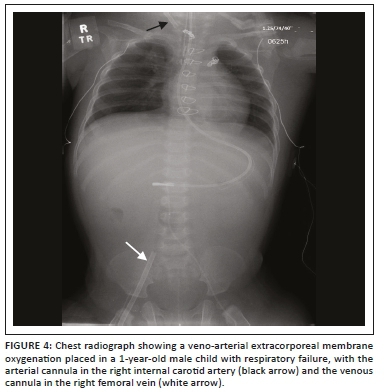

Extracorporeal membrane oxygenation (ECMO) is increasingly being employed in adult patients who fail to wean after cardiopulmonary bypass post-cardiac surgery, as well as in patients with severe respiratory failure. The intention of ECMO is to provide oxygenated blood while extracting carbon dioxide. The two main types of ECMO devices are veno-arterial (VA) ECMO and veno-venous (VV) ECMO. Both allow respiratory support, but only VA ECMO allows haemodynamic support, and hence only the latter is used for HF. In VA ECMO, deoxygenated blood is siphoned off from a vein and oxygenated blood is returned to an arterial vessel (aorta for central VA ECMO and proximal femoral, axillary or subclavian artery for peripheral VA ECMO), while in VV ECMO, the oxygenated blood is returned to a systemic vein or the right atrium. Following appropriate placement, the cannulas are sutured to the skin to prevent displacement and malposition. Radiographs of the chest and abdomen are performed to ensure correct cannula positioning.

In VV ECMO, the femoral cannula tip should be at the junction of the inferior vena cava (IVC) and the right atrium (RA), and the internal jugular vein (IJV) cannula tip at the junction of the superior vena cava (SVC) and the RA. The VV ECMO dual lumen cannula (e.g. Avalon Elite) is inserted through the right IJV into the RA, with the tip in the IVC (Figures 2 and 3). Cannulation sites for VA ECMO cannulas depend on the device configuration, with femoral-femoral being the commonest3,6 (Figure 4). A change in the position of the cannula with reference to an adjacent bony landmark on subsequent radiographs should prompt the radiologist to check for ECMO malfunction. Misplacement of the ECMO cannula can lead to vessel obstruction or occlusion (e.g. SVC obstruction). Other complications that have been reported include gas emboli, thrombosis of veins or arteries, cerebral ischaemia or stroke and haemorrhage because of anticoagulation.6 A summary of the various ECMO configurations and their indications are elaborated in Table 1.